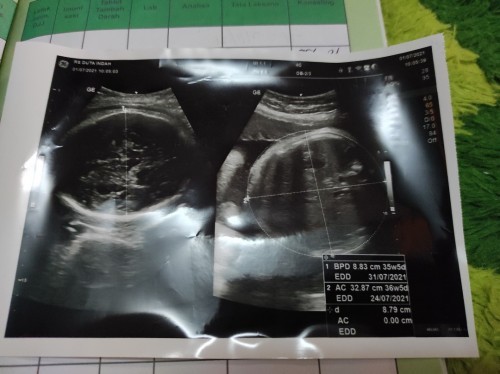

Sedikit cerita para pejuang bumil, aku baru saja menikah tgl 04 Oktober 2020 , Alhamdulillah Allah mempercayai kami untuk mendapatkan momongan yang memang kami dambakan sebelumnya. Sedikit cerita tentang kehamilan saya, Ketika itu saya sedang merasa tidak enak badan panas dingin dan lemas lalu saya periksa dengan test pack, saya lakukan ketika bangun tidur , lalu saya test pack hasilnya garis 2 dan yang satu sangatlah buram baik lah saya mulai panik dan mencari tau lewat google lalu minggu berikutnya karena seharus nya saya haid sebelum tgl 14 November, lalu saya test kembali menggunakan test pack compact dan ternyata hasilnya negatif, dan yang terakhir ini saya sudah telat seminggu dan ketika itu saya sedang merasa pusing sekali lalu paginya saya test pack dan hasilnya garis 2 Alhamdulillah, Allah maha baik , besoknya saya periksa ke dokter tapi ternyata belum bisa di lihat dalam USG karena masih belum kelihan bun ##bantusharing #firstbaby #Nanya #mommybuntu #pregnancy